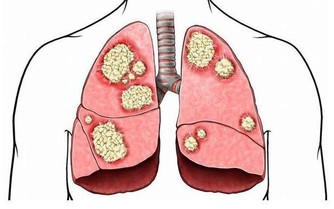

任何試圖更改生物鐘的行為,都將給身體留下莫名其妙的疾病,20、30年之後再後悔,已經來不及了。一、晚上9-11點為免疫系統(淋巴)排毒時間,此段時間應安靜或聽音樂。二、晚間11-凌晨1點,肝的排毒,需在熟睡中進行。三、凌晨1-3點,膽的排毒,亦同四、凌晨3-5點,肺的排毒。

此即為何咳嗽的人在這段時間咳得最劇烈,

因排毒動作已走到肺,不應Medicine,以免抑制廢積物的排除。